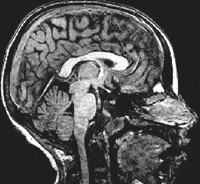

Kids’ Brain Development Charted as They Grow Up

First MRI Data Release on Young Children, Brain Chemistry

A landmark, multisite NIH-funded neuroimaging study of brain development in healthy, normally-developing children has posted its third release of data. This is the first release from the magnetic resonance imaging (MRI) study to include data from very young children — birth to 4 years old — and snapshots of brain chemistry at key developmental milestones. The data is accessible to qualified researchers via the NIH Pediatric MRI Data Repository website.

Similarly, through its data repository, the multi-institute NIH Pediatric Magnetic Resonance Imaging (MRI) Study of Normal Brain Development is sharing scan data and clinical/behavioral measures from a representative sample of healthy, typically-developing children, and providing researchers access to shared image processing tools. The study collected data between 2001 and 2007 from more than 500 children, spanning infancy to young adulthood, at 3-10 time points. Data is being released in stages.

The third data release includes longitudinal imaging and clinical/behavioral data for children ages 7 days to young adult. MRI scan data is accompanied by corresponding data from physical neurological examinations, behavioral ratings, neuropsychological testing, structured psychiatric interviews, and hormonal measures from urine and saliva samples. This is the first release to include data from a technique called MR spectroscopy, a type of MRI scan that measures the levels of certain bi-products of metabolism that can be used to gauge the health of brain tissues.